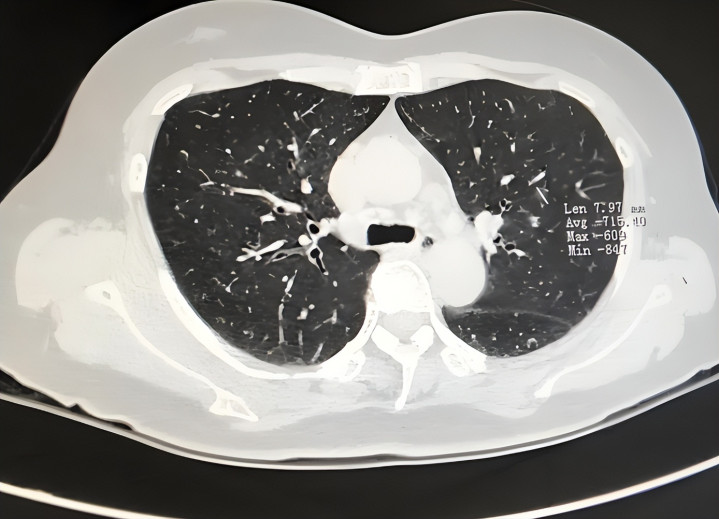

58岁的老周在体检中心门口这样说时,口吻很详情。闲居他不抽烟、不伤风,偶尔爬楼会喘,他只当“年岁到了”。直到一次单元低剂量胸部CT,诠释领导肺部小结节并伴轻度肺气谈改动,他才呆住:蓝本肺部问题,并不总所以咳嗽开场。

从指南共鸣看,肺部疾病早发现依赖两件事:识别非典型特别 + 实时作念模范检讨(如低剂量螺旋CT、肺功能等)。尤其是年龄增长、有抽烟史或永久油烟/粉尘露馅的东谈主群,更不可只盯着“咳没咳”。

到正规病院呼吸科就诊,勾通病史、体格检讨,按需选择低剂量胸部CT、肺功能、血旧例及炎症观念。不要一上来就反复拍片,也不要永久不查。

一般合计,年龄偏大且有永久抽烟史、干事粉尘露馅、肺癌家眷史者,应喜爱年度筛查。对部分高风险东谈主群,模范的低剂量CT可擢升早期发现率。